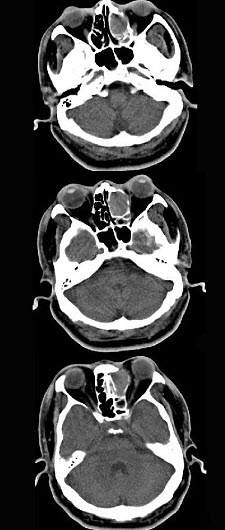

男,34岁,头痛、头晕3个月余,CT检查如图,最可能诊断为()。

A、筛窦癌

B、筛窦炎

C、筛窦息肉

D、筛窦乳头状瘤

E、筛窦黏液囊肿

正确答案:

E